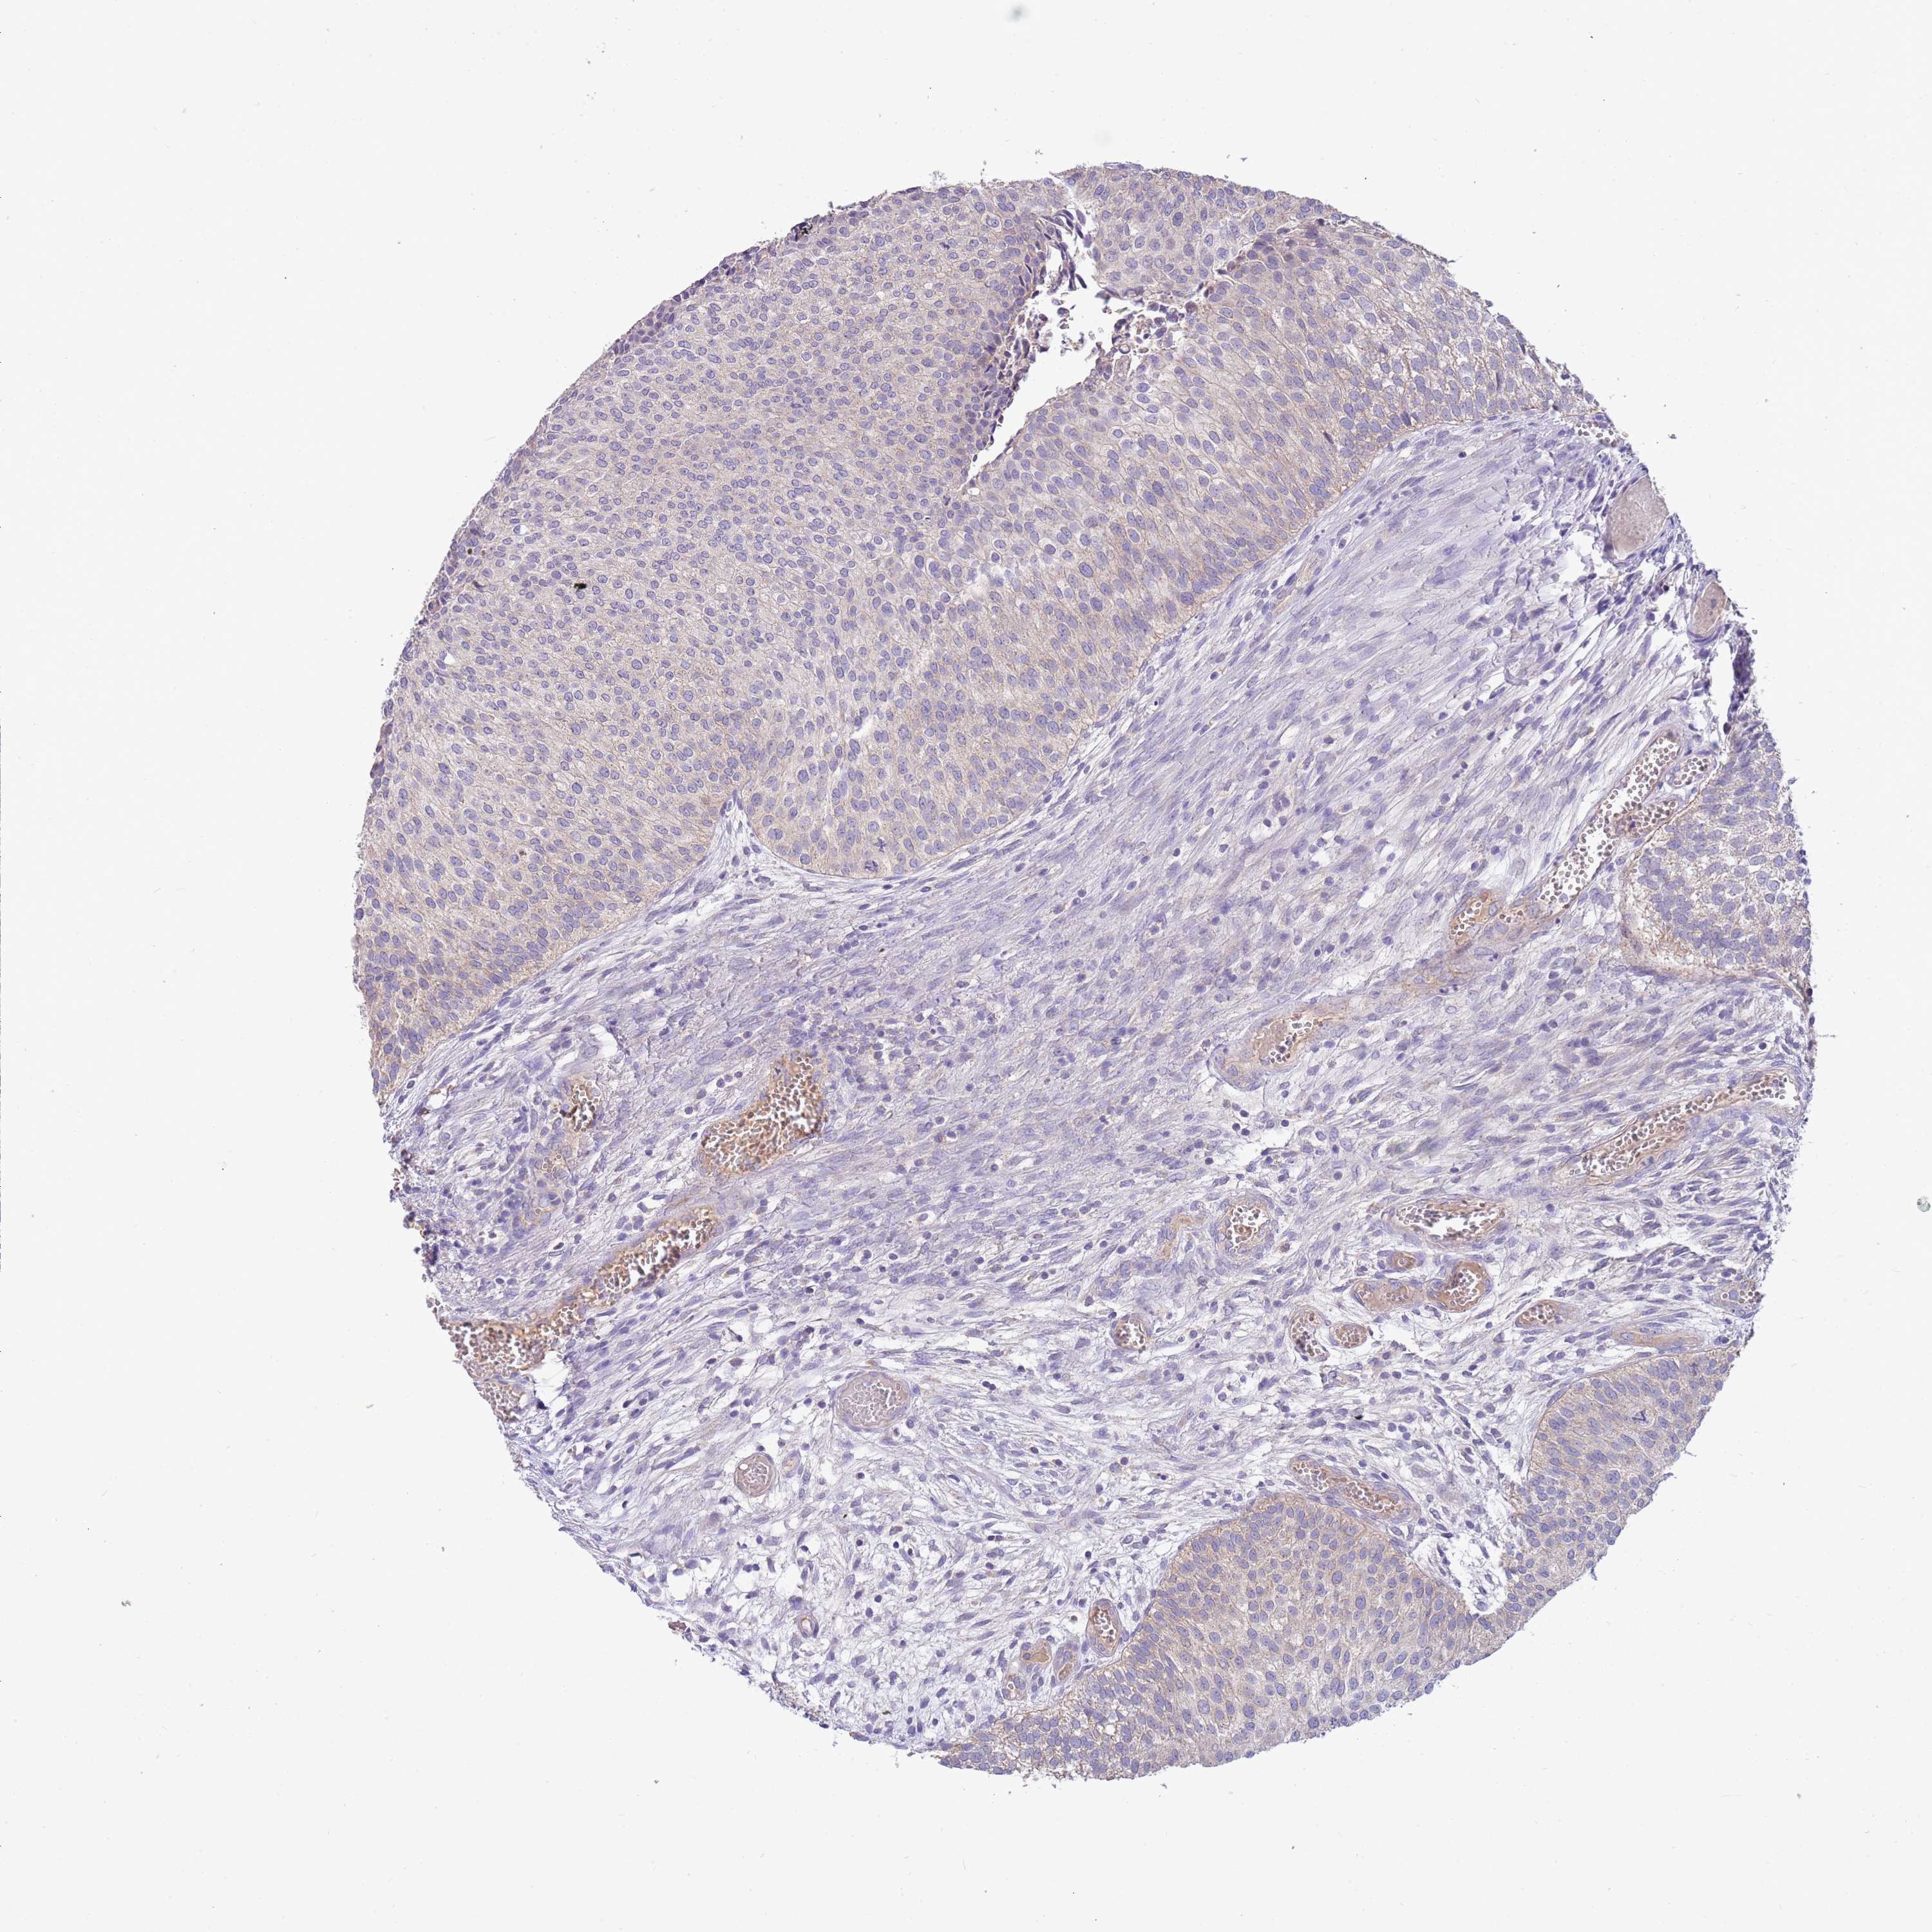

UROTHELIAL CANCER - Protein expressioni

A mouse-over function shows sample information and annotation data. Click on an image to view it in a full screen mode. Samples can be filtered based on level of antibody staining by selecting one or several of the following categories: high, medium, low and not detected. The assay and annotation is described here.

Note that samples used for immunohistochemistry by the Human Protein Atlas do not correspond to samples in the TCGA dataset.

Antibody stainingi

Antibody staining in the annotated cell types in the current human tissue is reported as not detected, low, medium, or high, based on conventional immunohistochemistry profiling in selected tissues. This score is based on the combination of the staining intensity and fraction of stained cells.

Each image is clickable and will lead to virtual microscopy that enables deeper exploration of all samples and also displays staining intensity scores, fraction scores and subcellular localization as well as patient and tissue information for each sample.

Antibody HPA021281

Staining

High

Medium

Low

Not detected

Intensity

Strong

Moderate

Weak

Negative

Quantity

>75%

75%-25%

<25%

None

Location

Nuclear

Cytoplasmic/membranous

Cytoplasmic/membranous,nuclear

Urothelial carcinoma, Low grade

Urothelial carcinoma, High grade

Urothelial carcinoma, NOS